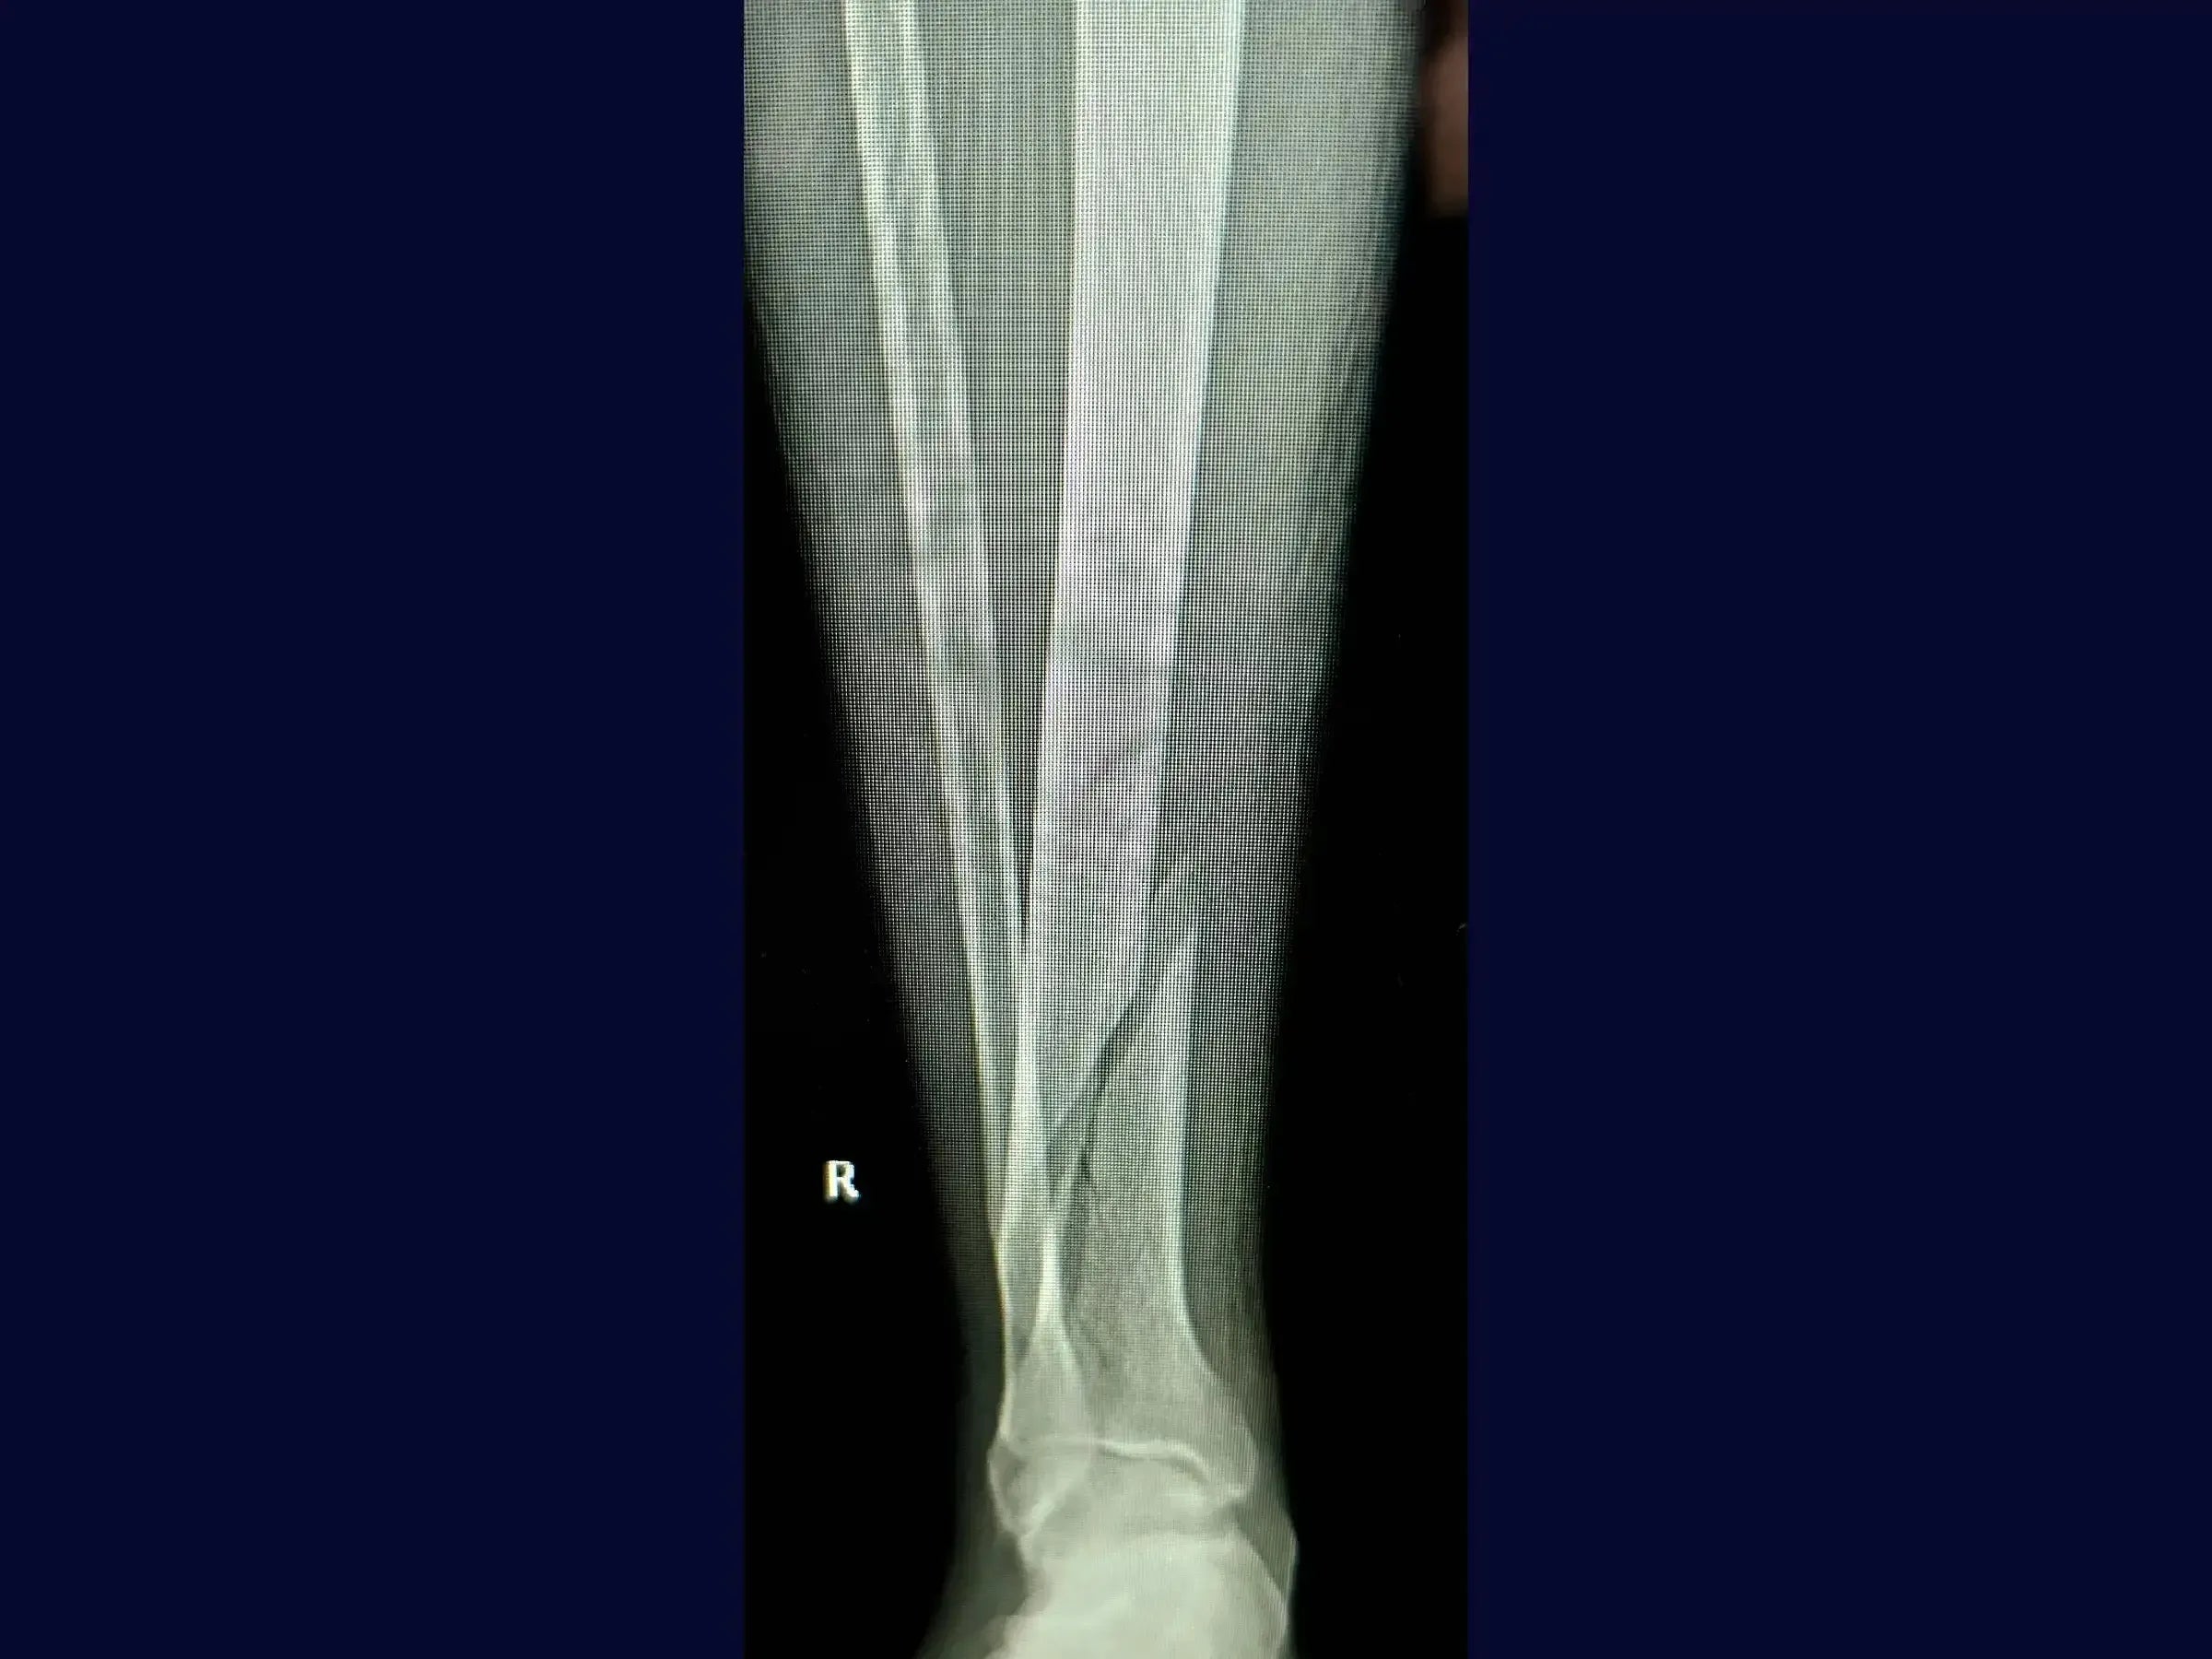

- Surgical treatment of diaphyseal tibial fractures with long oblique and spiral patterns.

- Optimized Preoperative Planning: Assessment of diaphyseal tibial fractures and associated fibula fractures through X-ray and computed tomography for precise planning.